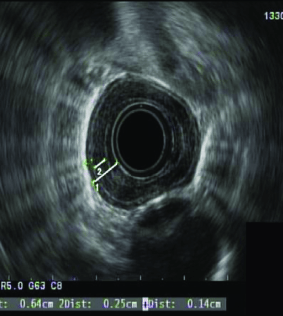

Endoskopik Ultrason Nedir?

Endoskopik Ultrason (EUS) iç organlara yönelik ultrason yapmak...